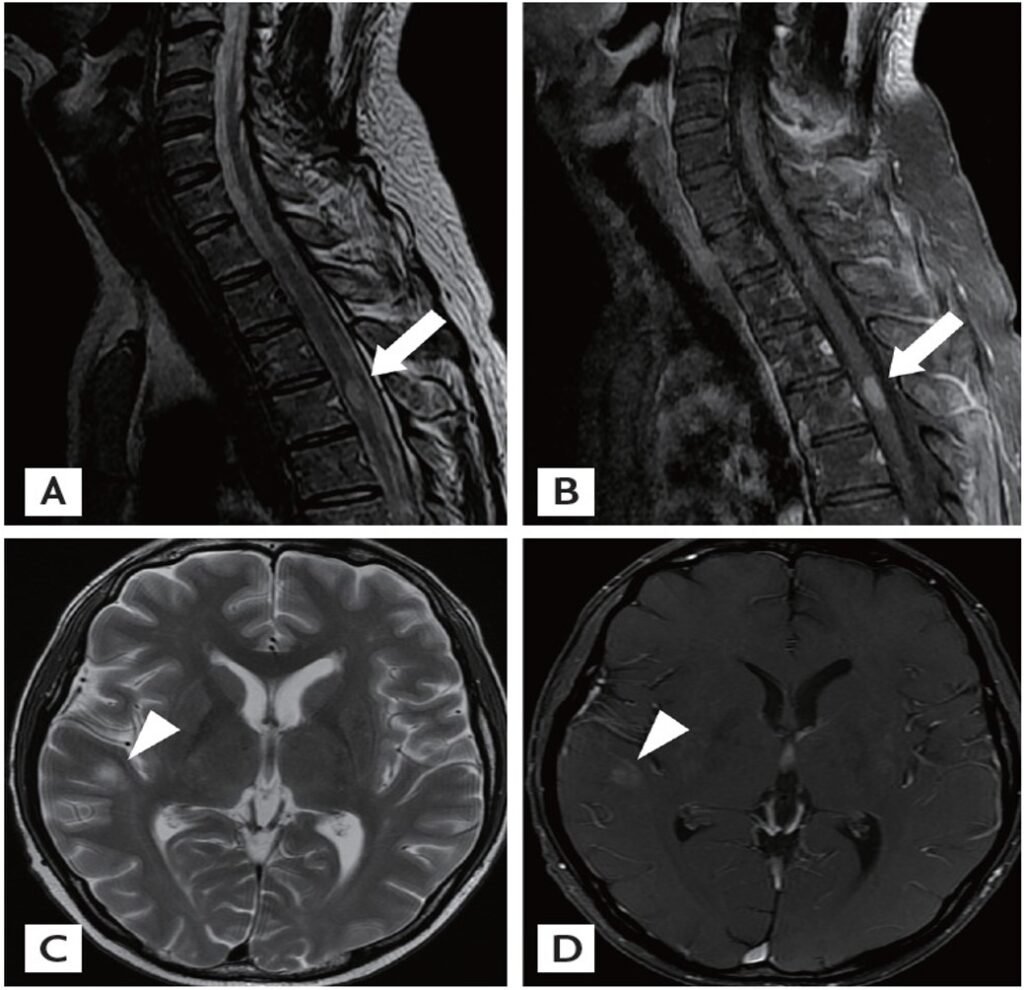

Spinal Cord Compression

This MRI of the spine shows evidence of spinal cord compression due to an extradural mass. The presence of significant edema around the cord suggests acute pathology. Recognizing these features is vital for timely surgical intervention to prevent neurological deficits.

Spinal Ependymoma (MRI Spine)

The MRI spine shows an enhancing intradural mass consistent with a spinal ependymoma, accompanied by associated edema. Differentiating these tumors from other intradural lesions is crucial for planning surgical management